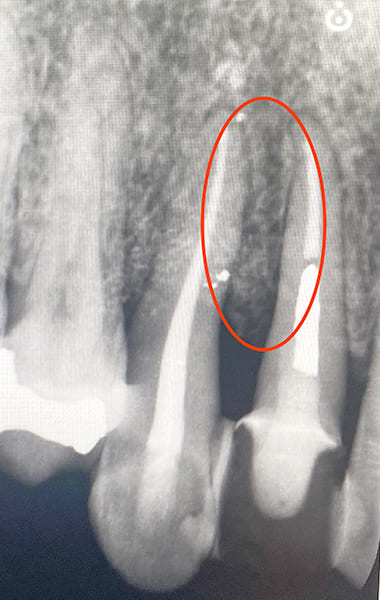

中等度・重度の歯周病は、従来の歯周基本治療だけでは改善が難しい場合が多く、抜歯が選択されることもありました。

しかし、現在ではエムドゲインなどの再生治療によって、骨を再生させ、抜歯を回避できる可能性があります。

進行度3

重度歯周病

(危険度★★★★★)

重度の歯周炎になると、歯がグラグラして、歯と接している歯茎がさらに腫れ、化膿が進みます。歯と歯の間が広がり、歯茎が下がって、歯が長く見えます。この段階の治療法は再生療法を用いて歯周組織の再生をはかるかことが多いです。しかし、ここまで進行すると抜歯になる可能性が高くなります。